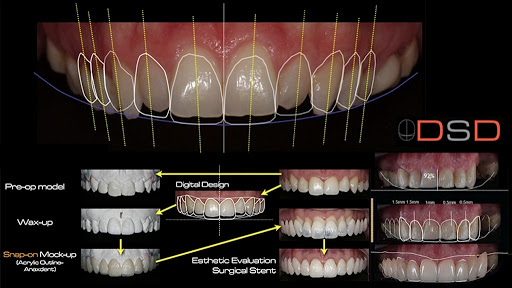

Il Digital Smile Design è un sistema di pianificazione digitale del sorriso ideata dal dott. Christian Coachman. Grazie a questo software si esegue un’analisi approfondita del rapporto tra proporzioni facciali e proporzioni dentali del paziente, ciò permette di individuare i punti deboli in un sorriso e di studiarne i possibili miglioramenti. L’utilizzo del software permette di coinvolgere nella progettazione anche gli stessi pazienti: grazie alla ricostruzione virtuale del sorriso che si vuol ottenere, si può avere un’idea concreta del risultato finale, senza dover attendere l’esito del trattamento.

- Fase 1 – Analisi: viene eseguita un’analisi del sorriso del paziente attraverso alcune foto e un breve video. L’integrazione di foto e video permette di tenere conto non solo della forma del viso in relazione ai denti, ma anche delle note espressive e della personalità dell’individuo, in modo da giungere a un risultato che sia il più personalizzato possibile.

- Fase 2 – Scansione: viene effettuata una scansione 3D della bocca del paziente. La scansione con scanner intraorale iTero, ci permette di individuare piccoli disallineamenti, rotazioni o diastemi facilmente correggibili con un breve trattamento di ortodonzia invisibile. Inoltre, il file che deriva dalla scansione viene condiviso con il Digital Smile Design (DSD), con cui possiamo ridisegnare completamente l’estetica del sorriso del paziente.

- Fase 3 – Prova: a questo punto il paziente avrà capito tutto quello che succederà nella sua bocca e quale sarà il risultato finale dei trattamenti, ma riuscirà ad apprezzare tutto ciò completamente? Secondo il nostro parere, per apprezzare davvero l’esito finale, il paziente deve prima “provarlo”. Come è possibile? Si rilevano due impronte tradizionali su cui si realizza una ceratura secondo i progetti fatti sul Digital Smile Design (DSD) e si stampa una mascherina attraverso la quale riusciamo a costruire, in pochi minuti, in bocca tutto quello che finora era solo un’immagine su uno schermo.

Adesso finalmente il paziente puoi vedere “dal vivo” il sorriso che avrà alla fine del trattamento, con i volumi delle labbra cambiati, le zone rugose tirate… Insomma potrà toccare con mano che non sta solo accettando di fare un allineamento dentale o delle faccette estetiche, ma che sta cambiando, in meglio, l’estetica del proprio viso.

Con l’ausilio di queste tecnologie integrate, scanner digitale iTero e DSD, si riesce a ottenere una grande predicibilità di trattamenti a volte complessi e un’eccezionale comunicazione col paziente che, finalmente, può seguire la terapia dall’inizio alla fine, previsualizzando il risultato finale e ottenendo grandi vantaggi anche in termini di tempo e di costi.